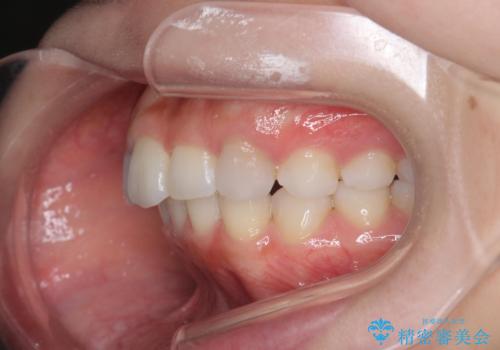

前歯のがたつき気になる。インビザラインモデレート

- 前歯のがたつきが気になるとの事で来院。

噛み合わせを確認したところ上の歯が全体的に前にある状態でした。

患者様は2のプランを選ばれたのでインビザラインモデレートで治療を行いました。

ガタつきがなくなり満足して頂けました。

矯正後は補綴装置をつけないと後戻りしてしまう可能性があるので

補綴装置をしっかりと装着する必要があります。